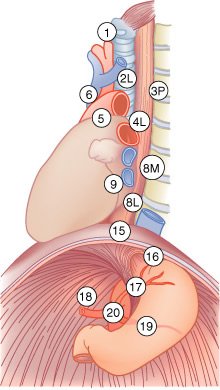

Mapa de linfonodos para câncer esofágico. A, Visão anterior. B, Visão lateral esquerda. C, Visão lateral direita. Estações ganglionares: l, supraclavicular; 2R, paratraqueal direito; 2L, paratraqueal esquerdo; 3P, mediastinal posterior; 4R, ângulo traqueobrônquico direito; 4L, traqueobrônquico esquerdo; 5, aortopulmonar; 6, mediastinal anterior; 7, subcarinal; 8M, paraesofagiano médio; 8L, paraesofagiano inferior; 9, ligamento pulmonar inferior; 10, hilar; 15, diafragmático; 16, paracardial; 17, gástrico esquerdo; 18, hepático comum; 19, esplénico; 20, celíaco A falta de serosa do esôfago tende a favorecer a extensão local do tumor.